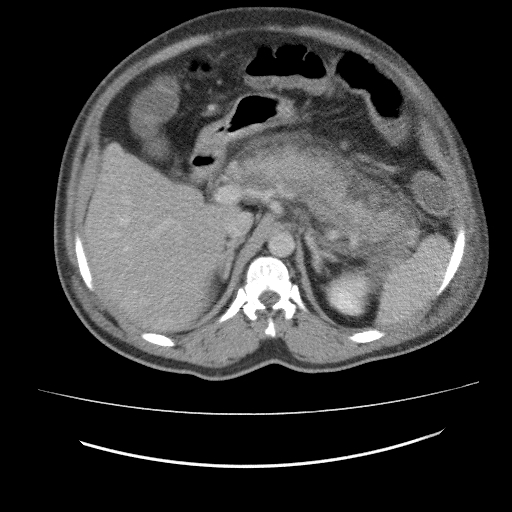

CT (PLAIN AND IV CONTRAST): ABDOMEN AND PELVIS